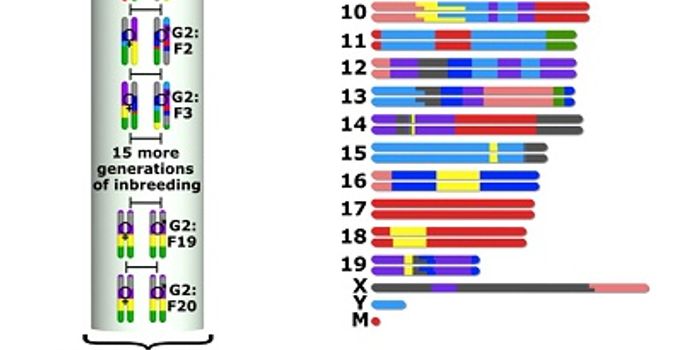

MAR 04, 2015Cell & Molecular BiologyEvolution brings improvements, but it's also a hotbed for lots of diseases that defy treatment.

We see this i ... -

SEP 21, 2022CancerPre-clinical modeling, often using laboratory mice, is essential in developing life-saving therapies to treat cancer and ...